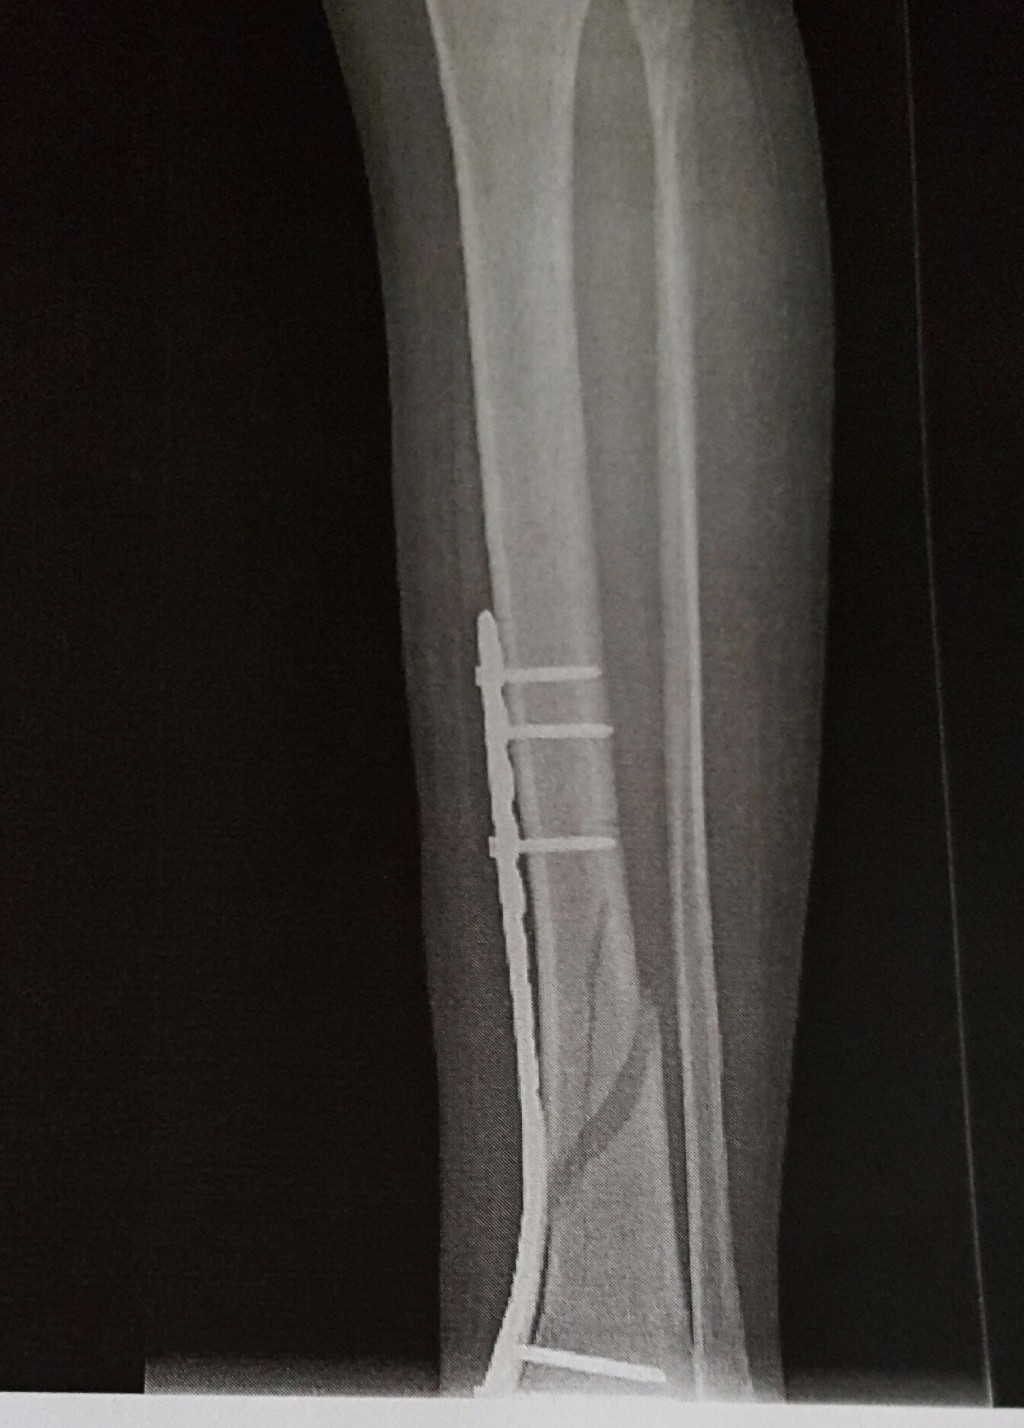

Перелом большой берцовой кости - серьезное повреждение, сопровождающееся болезненными ощущениями и нарушением функции ноги. На этой странице вы найдете много фотографий, позволяющих вам более детально изучить эту травму.

Большеберцовая кость рентген

Здесь представлены медицинские изображения переломов большой берцовой кости, сделанные врачами в процессе диагностики и лечения. Вы сможете увидеть, как выглядит этот тип травмы на рентгеновских снимках и других медицинских изображениях.